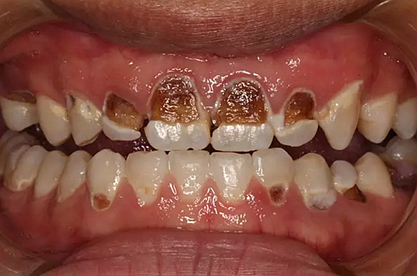

我們的主人今年才25歲,可卻從很小的時候就嗜好喝可樂等碳酸飲料,幾年下來,讓我們兄弟姐妹們整天浸在碳酸里受這蝕骨之痛,原本皎潔的外貌如今早己經是腐蝕不堪、丑陋無比,更有甚者,一些兄弟姐妹們已經病入膏肓,被病痛折磨奄奄一息。

下面是醫(yī)生眼中和ct下的我們

一身病痛啊

牙結石、牙齦炎癥、牙體殘缺、慢性牙髓炎、蛀牙......

才二八芳華的我們

已經滿目蒼夷